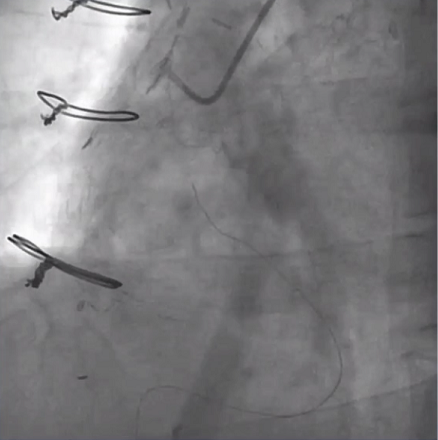

PCI过程:导丝冲浪技术通过侧支循环,应用反向CART技术通过闭塞段后2.0球囊扩张,随后出现室间隔支破裂(图4),行超声心动图可见室间隔巨大血肿形成,但患者血流动力学相对稳定,予以保守治疗继续观察。

图4 室间隔支破裂